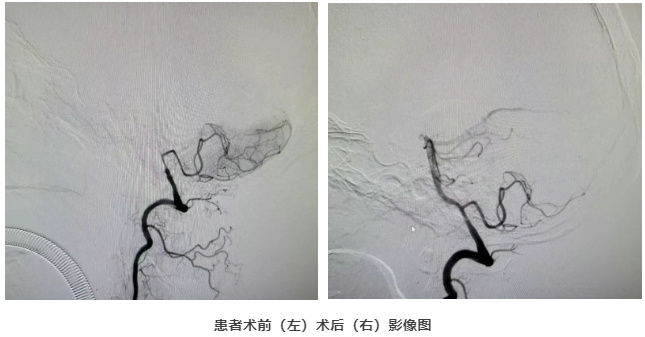

5月8日,手术室内只有仪器传出的滴滴声,在导管室精密的影像设备引导下,万曙亲自操刀,带领团队迎难而上。纤细的导管成为穿越险滩的方舟,小心翼翼地探入椎动脉深处。导丝在完全闭塞的血管内精准推进,每一次毫米级的移动都考验着术者的经验与手感。

最终,球囊成功抵达“堵点”并精准扩张!随着血流瞬间恢复的影像在屏幕上清晰显现,所有悬着的心终于落下。

凭借高超技术和对血管条件的精准评估,万曙团队做出了关键决策:血流恢复理想,暂不放置支架!整个惊心动魄的过程,仅用了约30分钟。